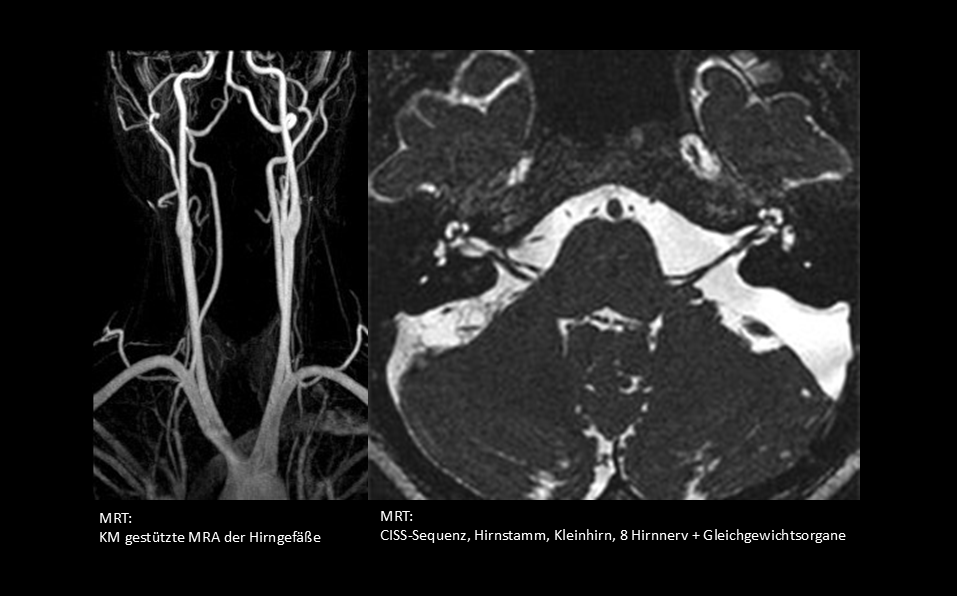

• Vestibuläres System (Labyrinthorgan, 8. Hirnnerv, Hirnstamm- und Kleinhirnbahnen)

Ein Drehschwindel (Karussellgefühl) im eigentlichen Sinne ist meist die Folge einer vestibulären Störung, also im Gleichgewichtsorgan im Innenohr oder seiner kommunizierenden Nervenbahnen. Häufige Ursachen hierfür sind der gutartige paroxysmale Lagerungschwindel (kurzer Drehschwindel z.B. beim drehen im Liegen), die Neuritis vestibularis oder der M. Meniere (zusätzlich meist Ohrgeräusch oder Hörminderung). Auch eine vestibuläre Migräe (zusätzlich meist Kopfschmerz) oder eine sog. Vestibularisparoxysmie (sehr kurze wiederkehrende Schwindelattacken) sind typische Erkrankungen dieses Systems.